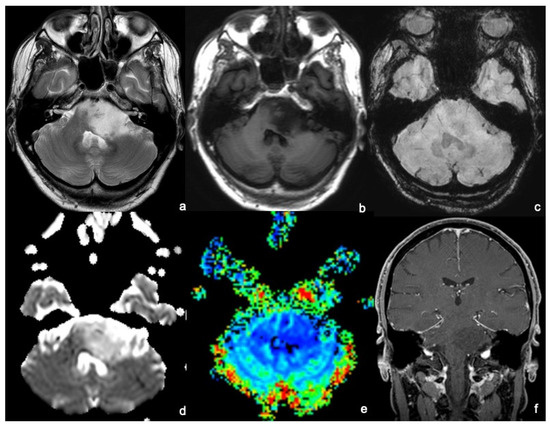

3.4.1. Exophytic Brainstem Gliomas (EBSGs)

3.4.2. Brainstem Gliomas Associated with Neurofibromatosis Type 1 (NFBSGs)